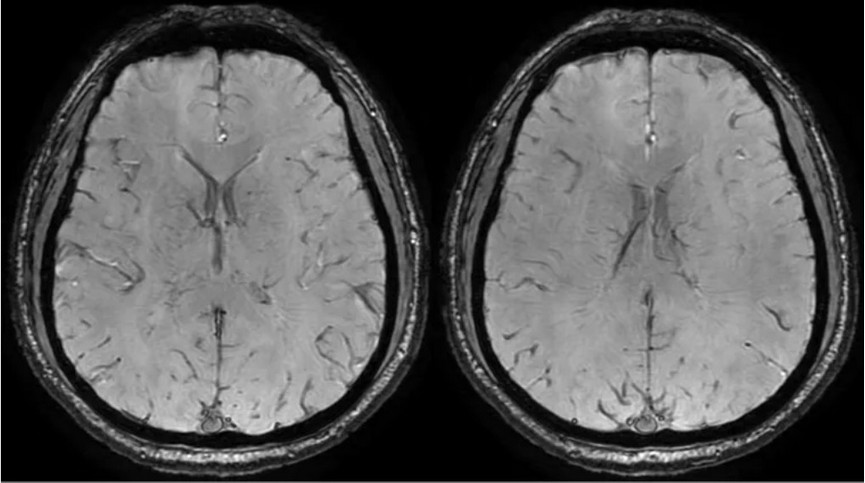

临床申请:颅脑平扫,静脉成像,磁敏感成像,颅内静脉血管黑血成像。

图像不逐一罗列,未见异常。

SWAN未见异常。

PC-MRV未见异常。

颅内静脉黑血成像,CUBE T1fs w/o +c,静脉窦未见异常。